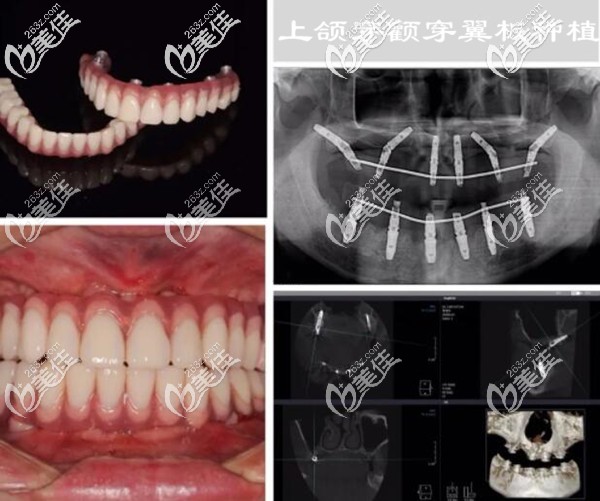

下面是我做穿顴穿翼板種植牙后的照片和CT片▼

因為,牙槽骨量太少,做傳統(tǒng)的種植牙要大量植骨,而且還要等3個月左右才能種牙。后來,上頜做的是雙側(cè)穿翼板種植,不用植骨;整個手術(shù)過程用了2個小時左右(不過手術(shù)前挺麻煩的,做了好多檢查)。

其實,我在做手術(shù)前也很緊張、很擔(dān)心,怕手術(shù)會有風(fēng)險,擔(dān)心留下啥后遺癥;不過看了術(shù)后多次復(fù)查的CT片,我終于放心了。